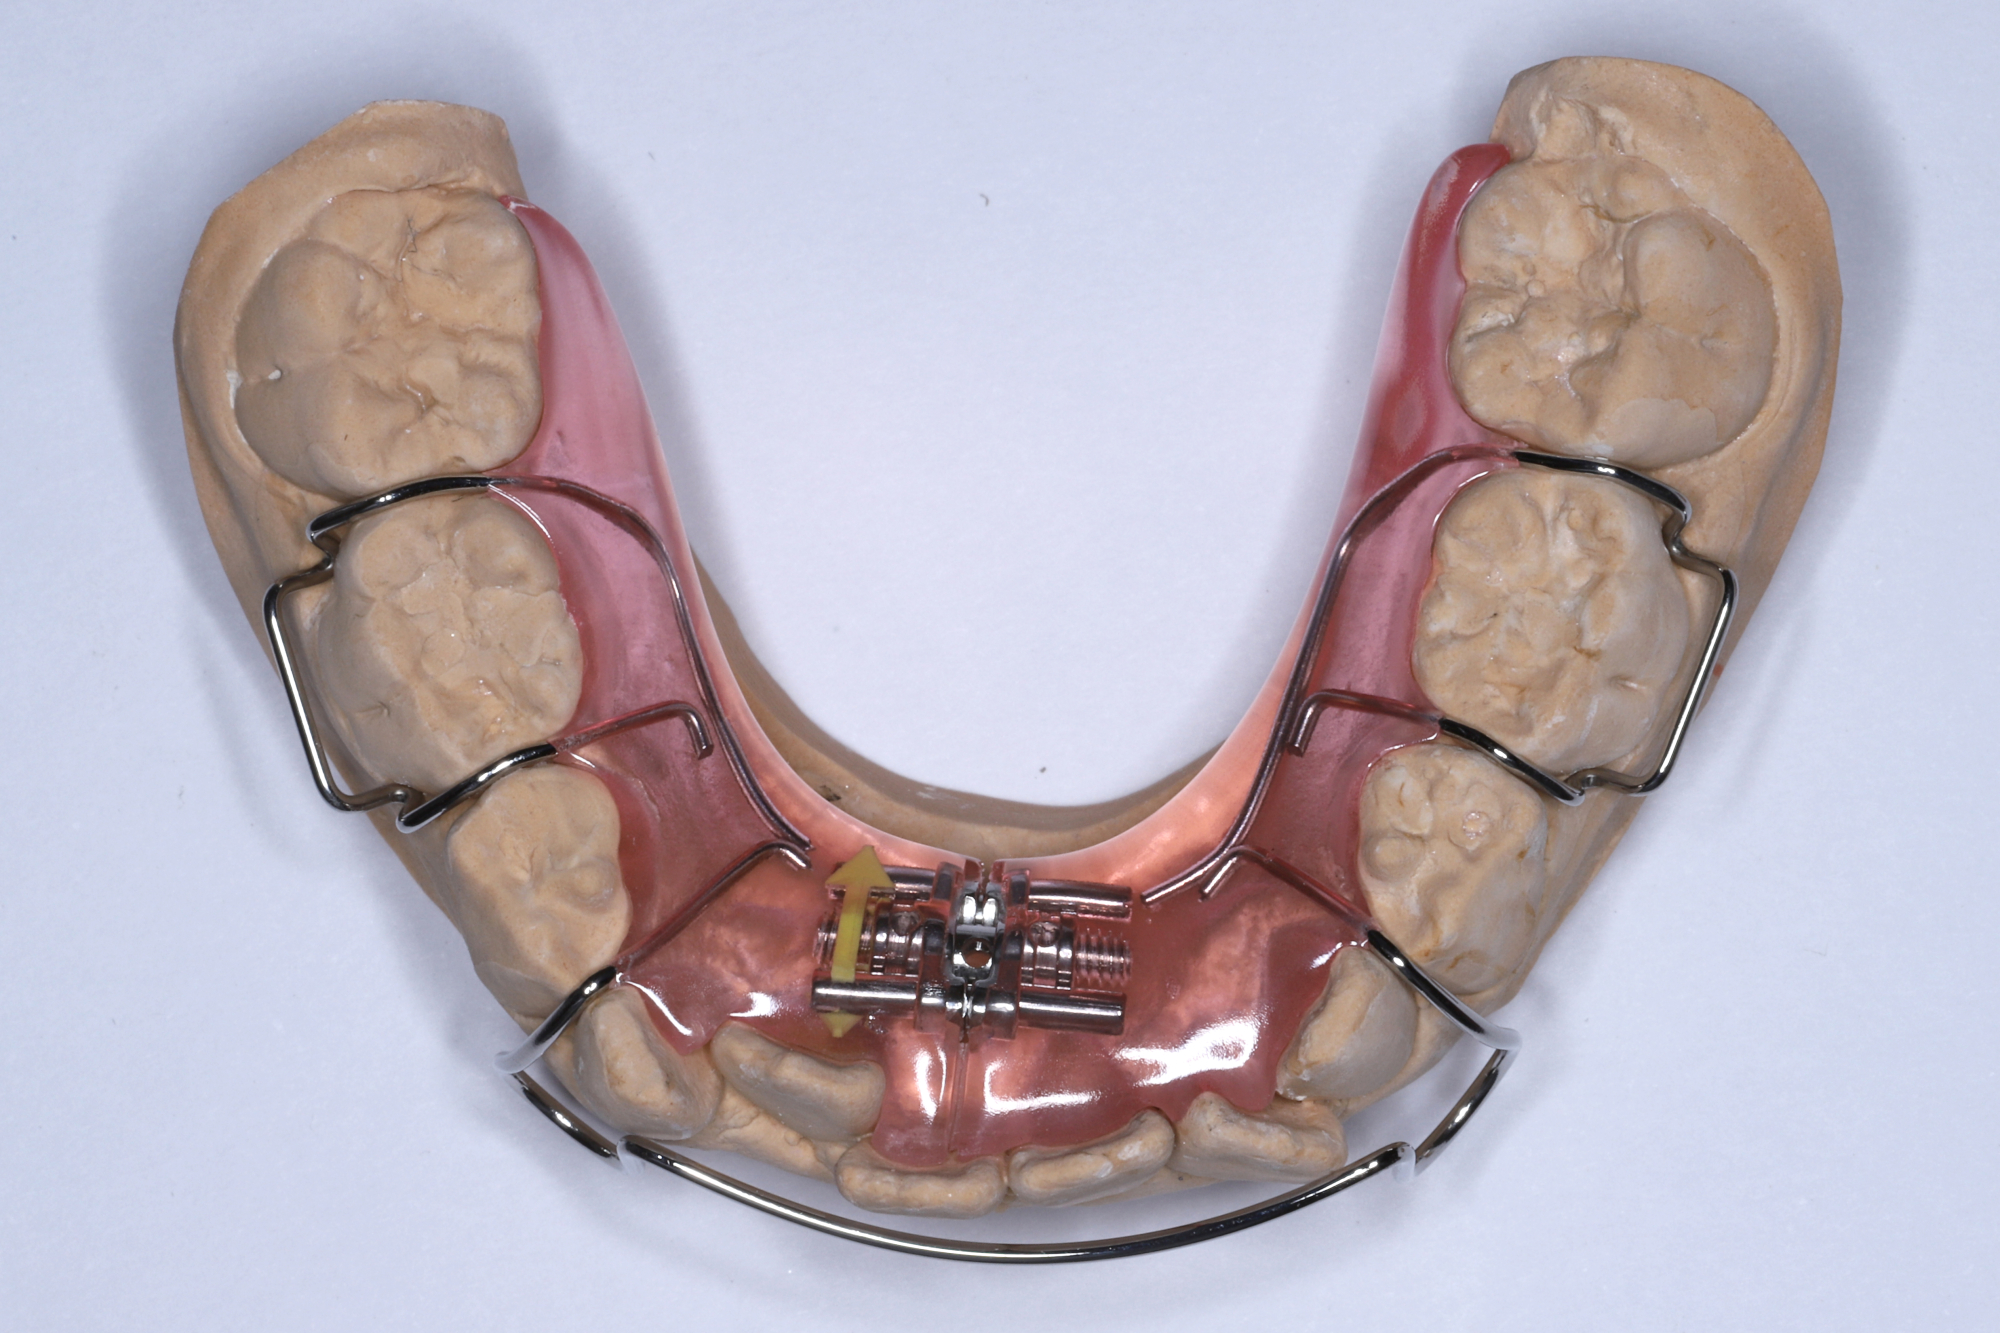

拡大床治療は以前よりヨーロッパを中心に行われていた治療法であり、いろいろな形の装置が用いられていました。 それらを整理し治療目標に応じてまとめたのがウィーンの歯科医シュワルツであり1938年に一冊の教科書にまとめたことでシュワルツの拡大装置と呼ばれるようになりました。 社会保障の充実したヨーロッパの各国では家庭で簡単にできる矯正治療法として広まり、北欧など自然環境が厳しい地域では通院回数が少なくて済む拡大床治療が一般開業医で保険診療として多く行われるようになりました。一方アメリカでは永久歯を抜歯してスペースを作り歯を画一的にキレイに並べる方法が確立され主流になっているため拡大床治療のように時間がかかり患者の装着状況によって治療結果が左右するような治療が行われることがありません。日本の歯科矯正治療学は歴史的にアメリカからの流れで発展してきたため矯正歯科専門で治療を行っている先生方の間では拡大床治療はあまり勧められていないのが現状です。簡単に云うと歯を抜かずに時間をかけて治療をするのがヨーロッパ的で、歯を抜いて短期間で完璧にキレイに歯を並べるのがアメリカ的と言えます。どちらの治療法も正しいと思いますのでご家庭、お子さんに合わせて治療法を選択する必要があります。

日本で行われている拡大床治療にも色々な方法がありますが当院での特長は最初に永久歯に生え替わる上下4本の前歯を奥歯の生え替わりが始まる前までに顎を拡大してきれいに並べることです。そのため拡大床治療の期間は小学校1年生頃から4、5年生頃までの間に限定しており、それまでに目的が達成できない場合には別の治療法に移行します。またゆっくりスペースを獲得するようにしているのも特長で2週間に1回ネジを回すようにしています。一般的には1週間にⅠ回ないし2回ネジを回すことが多いようです。ゆっくり進めるので一日の装着時間はお家にいるときと寝ている間だけにしています。学校や自宅以外での装着はせずゆっくり拡大していくので治療期間が長くなりますが後戻りは少なく確実になります。治療開始時期が大切ですので時期を逸した場合には拡大床治療は行いません。一般的に拡大床治療の評判が悪いのは開始時期が遅く、いつまでも治療を長引かせ治らないことによるものが多いようです。 拡大床治療はスペースを作って永久歯がならぶスペースを作ることが目標ですので細かい歯の向きや角度まで整えられないこともあります。そんな場合には別の矯正治療が必要になります。